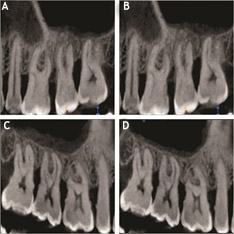

The CBCT measurements also followed a similar trend as depicted by the RVG. Group I exhibited an increase in the mucosal thickness at the end of 9 months while group II showed a reduction in the mucosal thickening of the maxillary sinus (Table 3) (Figure 1). For group I, there was an increase in the thickness of the sinus mucosa at all the points at the end of 9 months except for the AP, where a reduction in the thickening of the sinus mucosa was observed. However, it was not significant statistically at any point, except for the length of the thickened sinus mucosa, which showed a statistically significant increase as compared to baseline (P=0.0009). In group II at the end of 9 months the mean mucosal thickening reduction was highly significant at all the points (P<0.0001) and statistically significant for the length of the thickened mucosa (P=0.0081).

(A) CBCT analysis of mucosal thickening for group I at baseline. (B) CBCT analysis of mucosal thickening for group I at the end of 9 months. (C) CBCT analysis of mucosal thickening for group II at baseline. (D) CBCT analysis of mucosal thickening for group II at the end of 9 months.